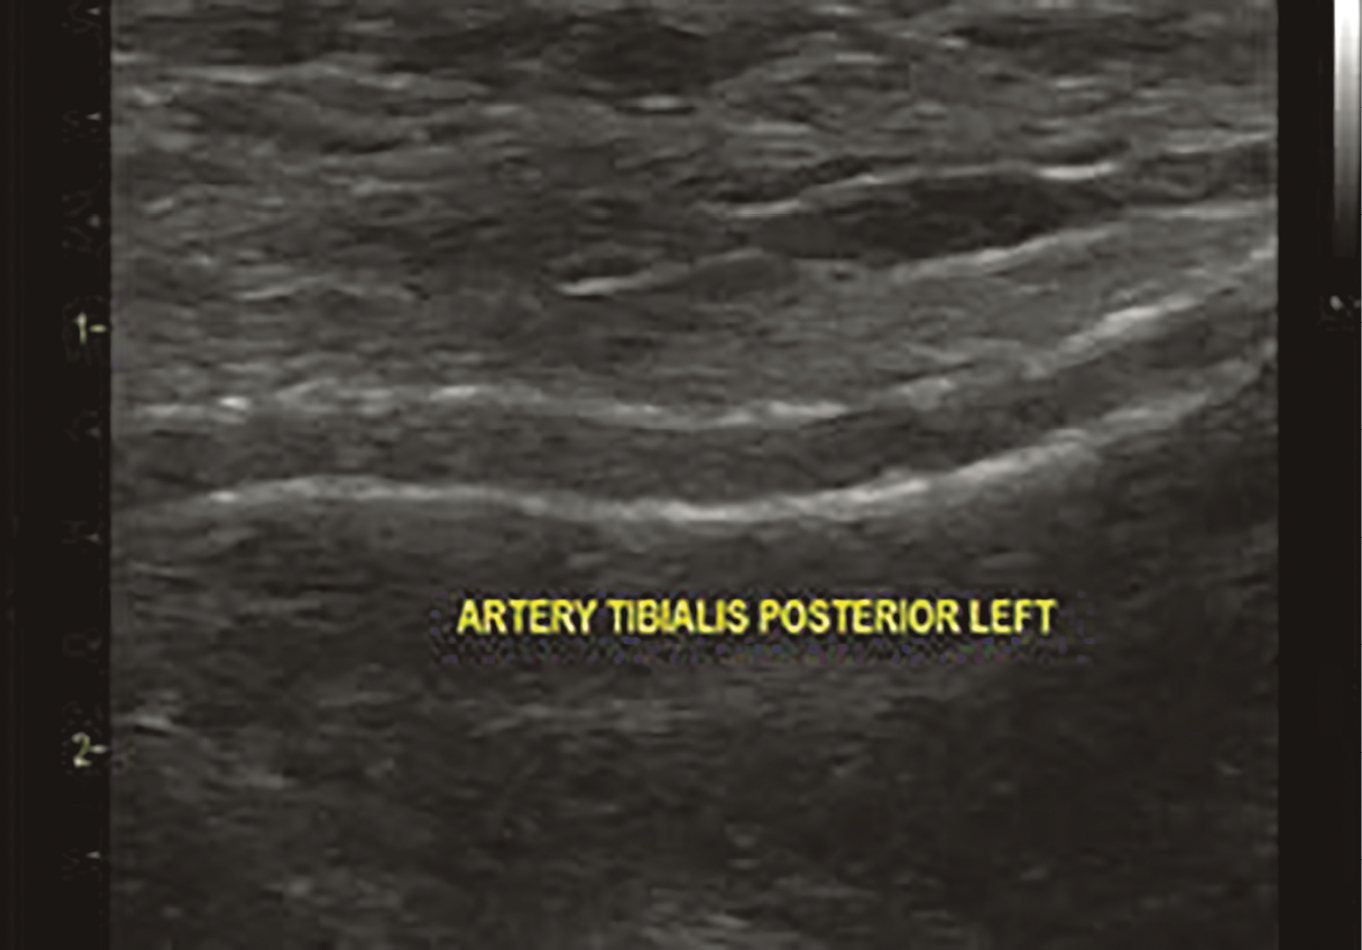

В настоящее время установлено, что медиакальциноз ассоциирован с СД, старением и повышенным риском развития хронической почечной недостаточности (ХПН), заболеванием коронарных артерий, ампутациями, высокой смертностью у больных СД [8]. Кальцификация средней оболочки артерий происходит независимо от атеросклеротического процесса, хотя и может сочетаться с ним [9]. В практической деятельности рассматриваются четыре основных вида кальцификации сосудистой стенки: кальциноз интимы, медиакальциноз, кальцификация клапанов сердца, кальцийфилаксия [10]. Наиболее важное с клинической точки зрения значение на сегодняшний день имеют два варианта кальциноза — медиакальциноз и кальциноз интимы [11]. В публикации Менкеберга указывалось, что структурные изменения были наиболее выражены в дистальных отделах сосудистого русла — артериях голеней и стоп. Считается, что выраженная степень склероза Менкеберга наблюдается при тяжелых метаболических и электролитных нарушениях, сопровождающих некоторые заболевания (СД, ХПН, гипервитаминоз D, остеопороз, прием варфарина, дефицит витамина К, ревматоидный артрит и некоторые другие), менопаузу и старение организма [7] (рис. 1, 2).

Рисунок 1. Эхограмма. В-режим. Кальциноз стенки задней большеберцовой артерии у пациента 73 лет с СД2 более 20 лет и хронической почечной недостаточностью.